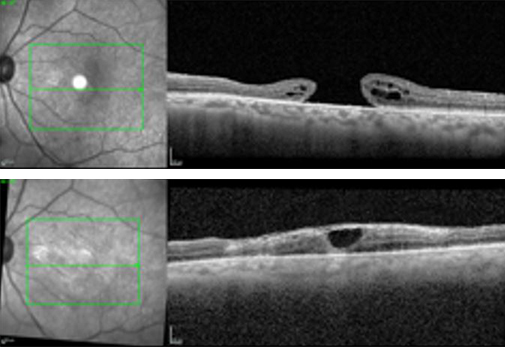

Que se passe-t-il lors du suivi à long terme ? Globalement, la MAL bien transplantée en overlay est inerte et reste visible des années après la transplantation (recul de 6 ans): la position et la forme initiales de la MAL après la résorption gazeuse restent inchangées par la suite ; les bords peuvent parfois s'enrouler, probablement en raison d'une réhydratation précoce des bords du disque de MAL sans déplacement secondaire. Sous silicone, une rétraction peut se produire, mais elle est probablement secondaire à de multiples facteurs (antécédents du patient / yeux multi-opérés) et peut-être à la tension superficielle de l'huile avec le disque de MAL (et des « réglages » du tamponnement) (figure 7).

figure 7

Figure 7 : Exemple modification disque MAL post opératoire